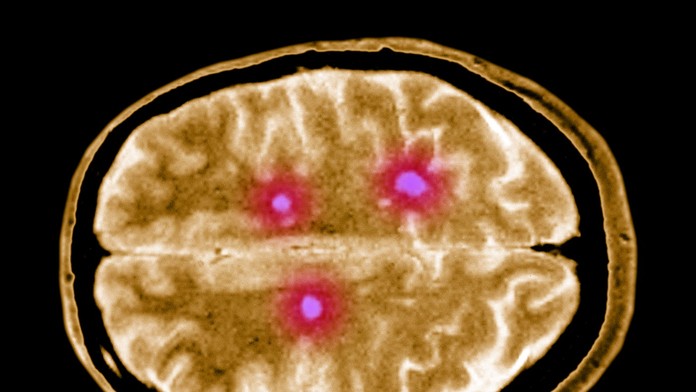

Ilustračná snímka. Zdroj: Profimedia.sk

Roztrúsená skleróza alebo skleróza multiplex je autoimunitné ochorenie, ktoré postihuje centrálny nervový systém človeka.

Konkrétne dochádza k poškodzovaniu ochranného obalu nervových vlákien v mieche a mozgu. Tento obal je tvorený myelínom, proces sa teda nazýva demyelinizácia. Postihnuté vlákna sú pritom zodpovedné za komunikáciu medzi mozgom a zvyškom tela, ich poškodenie tak môže mať trvalé následky.